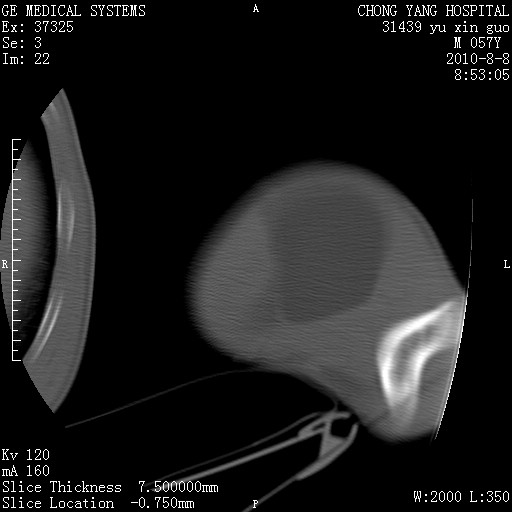

标题: CT28267:M57Y 上臂包块8年余。 [打印本页]

标题: CT28267:M57Y 上臂包块8年余。

包膜光滑、完整的脂肪密度肿块,支持脂肪瘤。

脂肪瘤。有ct值?